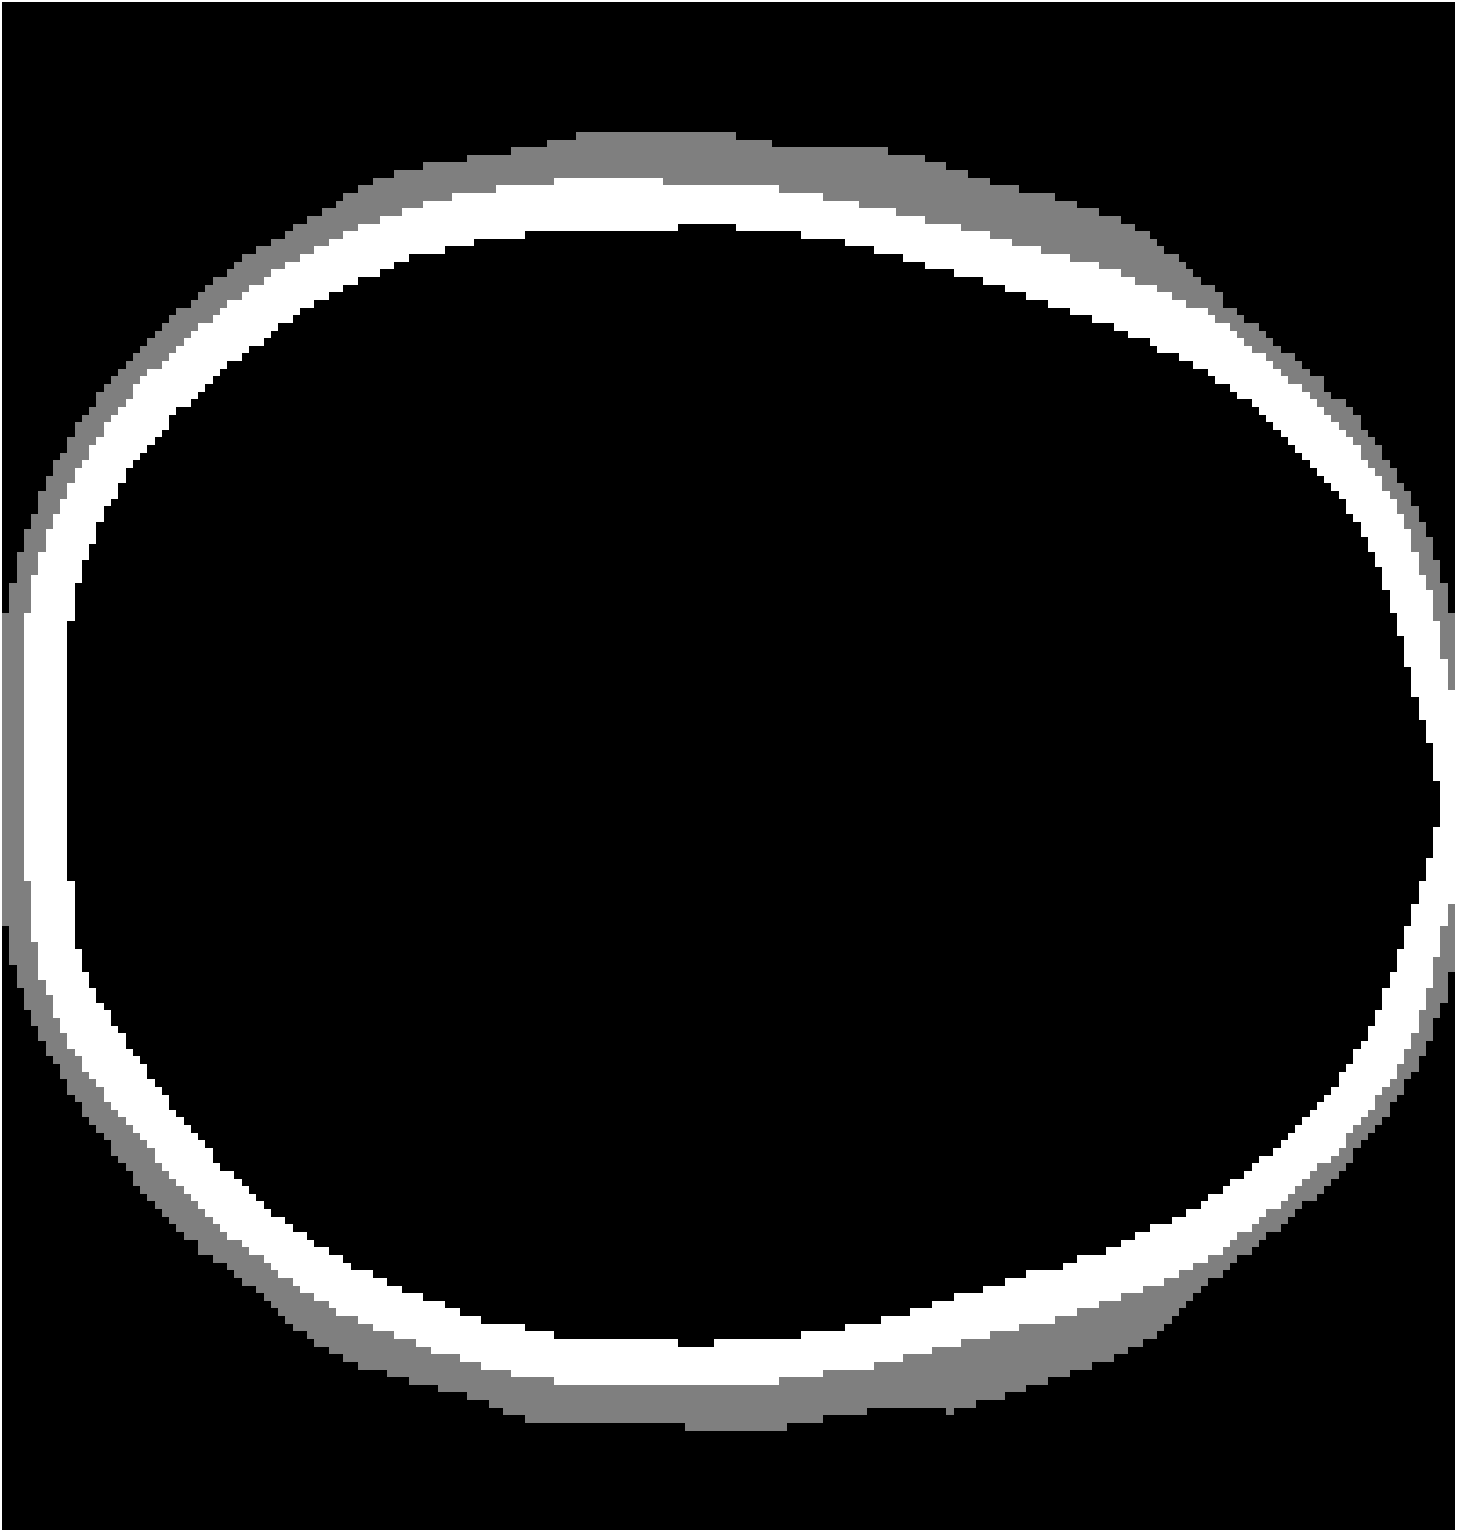

Refer to caption

(b) Full-transducer dataset

Figure 8: Stacked TRA Image with (a) Partial-transducer dataset and (b) Full-transducer dataset

To evaluate performance, we construct two acquisition setups from the same horizontal 2D slice of the phantom: (i) an idealized full-transducer dataset (Figure 4(b)) providing near-uniform coverage along the head contour, and (ii) a partial-transducer dataset (Figure 7) designed to reflect practical acquisition constraints. In the partial setup, a linear array with 51-element is repositioned around the head; for each view, the central element transmits and all other 50 elements receive. The partial setup includes 50 sweeps covering the full 360, meaning that for each sweep, the source and receivers rotate by 360/50=7.2360/50=7.2^{\circ}. Sweeping 50 views yields, per 2D slice, a channel tensor of shape (T,Ns,Nr)=(5001,50,50)(T,N_{s},N_{r})=(5001,50,50). The key distinction between these two datasets is their aperture: full-transducer provides near 360 coverage in a single placement, whereas partial-transducer attains coverage by aggregating neastest 50 receivers in a single placement, which is only around 36. Particularly, the partial-transducer setup includes only 50 sweeps, while the full-transducer setup uses all receivers covering the entire brain, with each transducer acting as a source in turn while the others serve as receivers. Compared to the full-transducer, the partial-transducer achieves coverage by combining a much smaller number of views. For each sweep, we generate the forward wavefield g(𝐱,t|𝐠){{g}}(\mathbf{x},t|\mathbf{g}) and the back-propagated wavefield p~(𝐱,t|𝐠)\tilde{{p}}(\mathbf{x},t|\mathbf{g}) and generate the TRA fragment with Eq. (7) (example in Figure 7). With the physical TRA method, the TRA fragment can be stacked to give the stacked TRA image. To validate the differences between the two datasets, we generated stacked TRA images using both datasets, as shown in Figure 8. As shown in Figure 8(b), the full-transducer dataset provides significantly greater detail in internal structures. Despite higher levels of noise and artifacts caused by the limited number of views, the partial-transducer dataset is still capable of capturing some meaningful tissue structures.